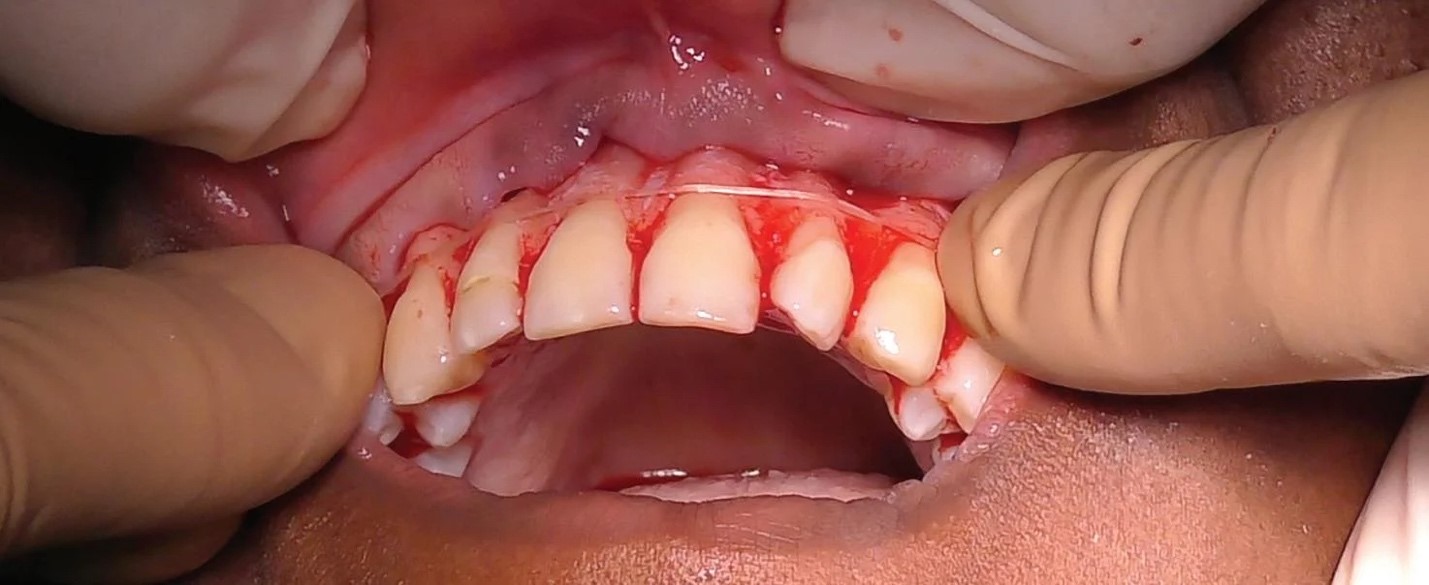

در دنیای امروز، پیوند لثه یکی از موثرترین راهحلها برای بازگرداندن زیبایی و سلامت لثهها به شمار میآید. این روش بهویژه برای افرادی که دچار تحلیل لثه و مشکلات مرتبط با آن هستند، میتواند نقش مهمی در بهبود وضعیت دهان و دندان ایفا کند. در شهر کرج نیز، به دلیل…

لیفت لثه در کرج

لیفت لثه در کرج یکی از روشهای پیشرفته دندانپزشکی است که به افرادی که از ناهنجاریهای لثه رنج میبرند کمک میکند تا لبخندی زیباتر و جذابتر داشته باشند. این روش که با نامهای مختلفی مانند جراحی لیفت لثه نیز شناخته میشود، برای برطرف کردن بیشازحد دیده شدن لثهها هنگام لبخند…